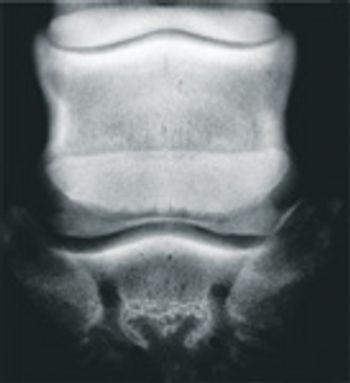

Back problems are a common cause of poor performance in all horses - especially competitive horses, whose jumping ability may be diminished.

Osteoarthritis is a common problem for the athletic horse and has been estimated to cause 60 percent of lameness cases in the athletic horse.